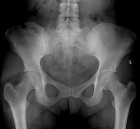

50 year old female presents with c/o enlarging mass in L buttock region. Hx of having had a mass excised from this same area five years earlier.

Zoom image: Radiological image Radiological image.